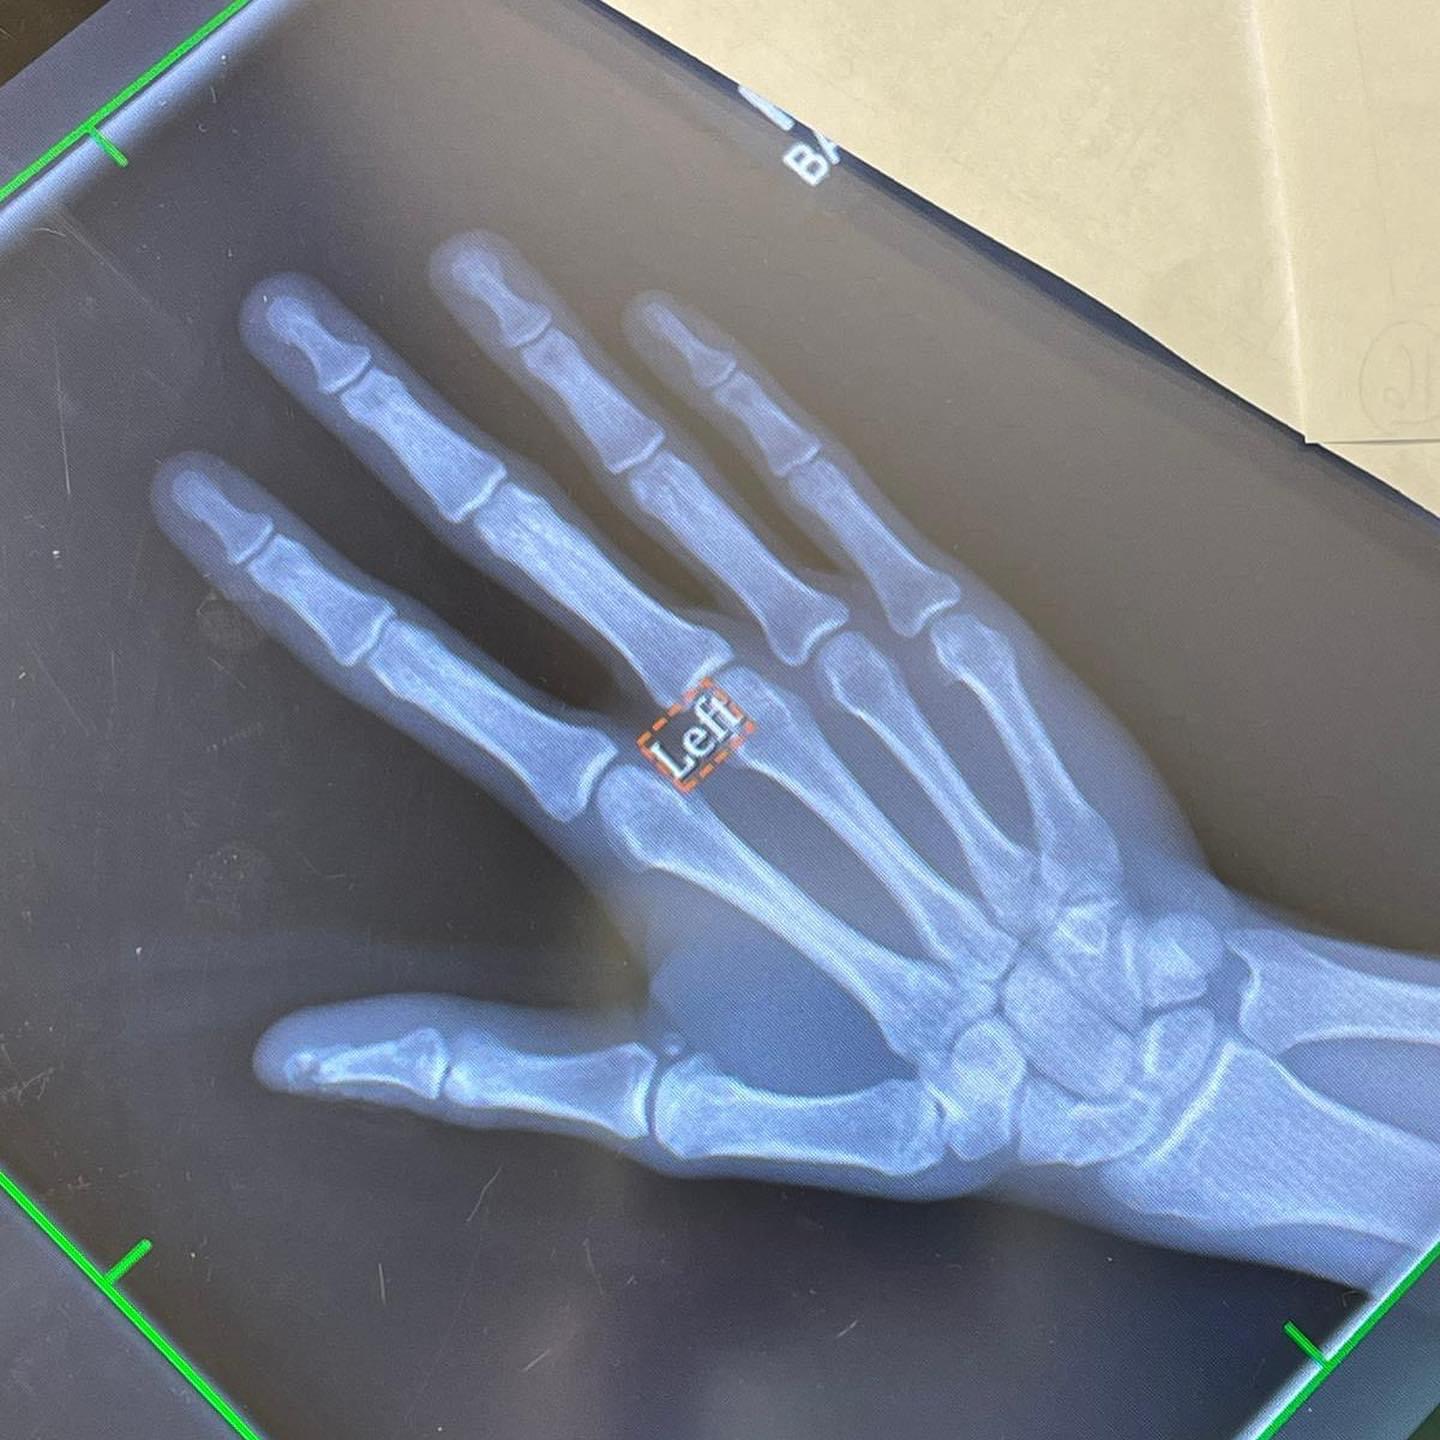

Malheureusement, Ludovic s’est fracturé le pouce le lendemain de son arrivée aux Etats-Unis en chargeant sa moto dans la remorque. Son doigt est resté coincé entre la couronne et le bras oscillant.